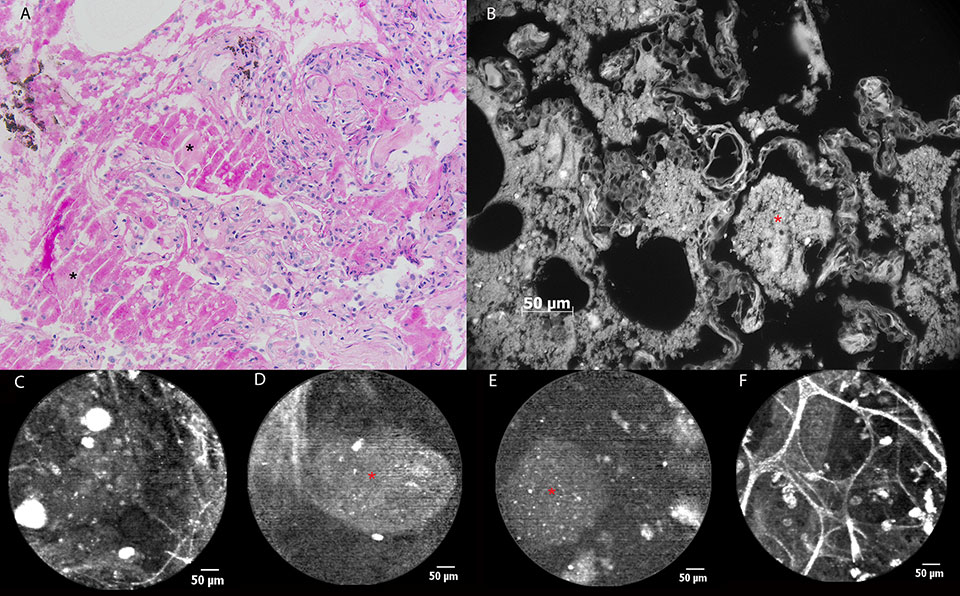

Figure 2

a) Still image of bronchial mucosa during white light bronchoscopy showing ulcerative lesions (arrows) at the level of the left main bronchus. b) pCLE imaging of normal bronchial tissue (blue area) consisting of longitudinally arranged elastic fibres and the orifice of a bronchial gland(asterisk). c) Distortion of the elastic fibre arrangement in areas of diseased mucosa (green area) during pCLE : loss of fibres and fibre disarray. d) pCLE imaging of an ulcer (orange area): complete loss of elastin with the appearance of highly fluorescent cellular structures. e) Histopathological sample showing respiratory mucosa with large areas of squamous metaplasia (asterisk). Local ulceration (centre of image) containing mycelium (encircled area), possibly aspergillus. Inflammatory stromal reaction containing a large number of neutrophils.

Figure 3

pCLE imaging in a patient with alveolar proteinosis. (a) Histopathological image of a transbronchial lung biopsy showing alveoli containing amorphous, eosinophilic material (asterisk). PAS staining confirms the presence of glycoproteins, almost pathognomonic for alveolar proteinosis. b) The glycoproteinaceous material shows autofluorescence during ex vivo AF microscopy at 365 nm (asterisk). c) pCLE image showing alveolar ducts, ‘submerged’ into a ‘milky’ background containing fluorescent particles measuring 30-60 µm. d) In some alveolar regions, bigger, oval-shaped particles (asterisk) measuring more than 100 µm in diameter can be seen during pCLE, corresponding to glycoproteinaceous material. e) Ex vivo pCLE imaging of the fluid collected during whole lung lavage showing similar fluorescent particles (asterisk). f) pCLE imaging 4 weeks after whole lung lavage : normal pCLE characteristics of the alveolar region. Hyperfluorescent cellular structures (20-30 µm) are persisting.

Figure 4

a) Chest CT scan of a patient with exacerbating dyspnoea, showing bilateral honeycombing with right sided predominance (filled arrow), patchy areas of ground glass opacity (open arrow) superimposed by thickened inter- and intra-lobular septal fibres. b) pCLE imaging performed ex vivo after introduction of the probe in the BAL sample. A large (200 µm) clump of fluorescent material (glycoprotein) (asterisk) is surrounded by smaller (20-30 µm) round opacities (arrow) with increased autofluorescence (macrophages). c) Histopathology on a thoracoscopic lung biopsy sample. The basic alveolar structures have been preserved (arrow). Presence of eosinophilic, PAS stain positive material containing crystalised cholesterol (asterisk).

A 56-year-old man without striking medical history was admitted to the intensive care unit (ICU) because of bilateral overwhelming pneumonia and sepsis, secondary to an influenza A infection. After 2 weeks of invasive ventilation, flexible bronchoscopy revealed the presence of multiple ulcerative lesions throughout the tracheobronchial tree spreading distally from the main carina (fig. 2a). pCLE imaging showed some areas of normal bronchial mucosa in the left main bronchus (i.e., longitudinally arranged elastic fibres and some orifices corresponding to the presence of bronchial glands [fig. 2b]). Elastic fibre disarray, total loss of elastic fibres, and appearance of redundant thin fibres and zones of denser autofluorescence were noticed in a bronchial ulceration, (fig. 2c). In some frames, fluorescent globular particles could be seen (mean diameter 22 µm), once again of a possible cellular origin (fig. 2d). Bronchial biopsies were taken, confirming the presence of fungal hyphae identified as Aspergillus fumigatus (fig. 2e). Fungal cultures of bronchial tissue were positive for the same infectious agent.

A 48-year-old male smoker with a medical history of alveolar proteinosis (fig. 3a), was referred to our hospital for a whole lung lavage. He had been suffering from increasing exertional dyspnoea of New York Heart Association (NYHA) class 3 for half a year. A computed tomography (CT) scan showed bilateral crazy paving and lung diffusion capacity (TLco) had decreased from 68% to 42% in a 10-month time period. On the occasion of the whole lung lavage, pCLE imaging was performed. During alveoloscopy the ‘healthy’ pattern of alveolar ducts could only rarely be observed. A dense ‘milky’ alveolar background was found in most of the pulmonary acini, containing hyperfluorescent particles measuring 30-60 µm (fig. 3c). In some alveolar regions, bigger, oval shaped masses measuring more than 100 µm in diameter could be seen (fig. 3d). Throughout all lung segments examined we found hyperfluorescent cellular structures (measuring around 20 µm), corresponding to the alveolar macrophages seen in (healthy) smokers (2). When the confocal probe was put into the fluid which had been recovered during the whole lung lavage, similar findings could be described apart from the obvious fact that no alveolar ducts could be seen (fig. 3e). Bronchoscopy with pCLE imaging 4 weeks after whole lung lavage showed the reappearances of normal pCLE characteristics of the alveoli: clearly distinguishable alveolar duct openings and the presence of some highly fluorescent cells (fig. 3f). In vivo pCLE images and images obtained after ex vivo autofluorescence microscopy on the biopsy specimens (wavelength 365 nm) showed similar findings consisting of larger areas of non-cellular material (+/– 100 µm) with some brighter round opacities inside (+/– 20 µm) (fig. 3b).

The case of a 63-year-old non-smoking female patient with diffuse interstitial lung disease of unknown aetiology added more to this concept. Chest CT scan showed bilateral honeycombing with right sided predominance, patchy areas of ground glass opacity superimposed by thickened inter- and intra-lobular septal fibres (fig. 4a). During the flexible bronchoscopy, bronchoalveolar lavage (BAL) was performed for immunological research. When the confocal probe was inserted into the lavage fluid after bronchoscopy, the formerly described pattern was recognised, suggesting, indeed, an alveolar proteinosis (fig. 4b). Thoracoscopic lung biopsy confirmed the diagnosis of an alveolar proteinosis afterwards (fig. 4c).

The cases of alveolar proteinosis demonstrate that it is not only elastic fibres which can generate autofluorescence after ‘excitation’ by a laser beam at the given wavelength, but also that other proteins can induce, in this case a specific, pCLE pattern. Moreover, our findings in both these patients are very similar to what has been published by Salaün et al. in the European Respiratory Journal, describing pCLE findings in a smoker with alveolar proteinosis [7]. We add to those findings that the presence of hyperfluorescent material in these patients seems to be independent of their smoking status and that a mere examination of the lavage fluid could be sufficient to diagnose this disease.

Images obtained from ex vivo autofluorescence microscopy (fig. 3b) strikingly resemble the ones generated by in vivo pCLE imaging. This can be explained by the fact that the ex-vivo technique can use a laser beam with a wave length in the same range as ex vivo pCLE to generate autofluorescence. This doesn’t only confirm what is observed using pCLE, but could also make it possible to correlate in vivo findings with ex vivo autofluorescence and hence to some extent with light optical histopathology.